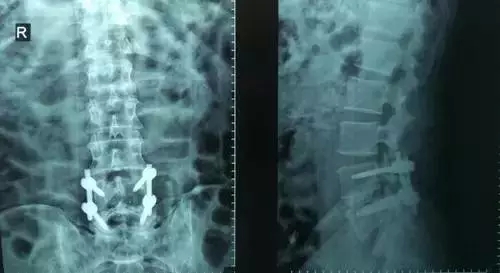

劉志安副院長所說的“微創(chuàng)小切口”就是通道下髓核摘除植骨融合經(jīng)皮內(nèi)固定術(shù)。其原理就是利用MIS-TLIF技術(shù)微創(chuàng)治療腰椎疾病,不但能達(dá)到開放手術(shù)的效果,且切口及創(chuàng)傷為開放切口的1/3,術(shù)中出血量少,患者術(shù)后可以恢復(fù)更快。

劉志安副院長將具體的手術(shù)過程向朱先生做了介紹,朱先生也同意了這個“微創(chuàng)小切口”手術(shù)。于是在術(shù)前的精心準(zhǔn)備之后,劉志安副院長協(xié)同其他醫(yī)護(hù)人員為朱先生進(jìn)行了手術(shù)。術(shù)后,朱先生的切口愈合良好,腰部疼痛消失,小腿麻木感也漸漸緩解。“手術(shù)后傷口略微有點痛,現(xiàn)在已經(jīng)完全不痛了,這種輕松的感覺已經(jīng)好久沒有了,真是萬分感謝劉院長。”在病房內(nèi),一臉笑容的朱先生如是說。

據(jù)劉院長介紹,MIS-TLIF技術(shù)是經(jīng)椎旁肌間隙入路運用脊柱內(nèi)鏡或?qū)S猛ǖ佬醒甸g盤切除、椎管減壓、植骨內(nèi)固定術(shù),是一項應(yīng)用廣泛、技術(shù)成熟的脊柱微創(chuàng)手術(shù)方法。本技術(shù)可以完成與傳統(tǒng)手術(shù)完全相同的椎間盤切除、椎間植骨融合內(nèi)固定等操作。手術(shù)切口一般3-5厘米,本手術(shù)方式可有效避免傳統(tǒng)手術(shù)對腰背肌肉的損傷,患者術(shù)后腰背部疼痛輕、恢復(fù)快,手術(shù)效果優(yōu)于傳統(tǒng)手術(shù),治療后1-3天即可下床活動。本技術(shù)適于大部分的腰椎間盤突出癥、腰椎管狹窄癥、腰椎滑脫癥等。